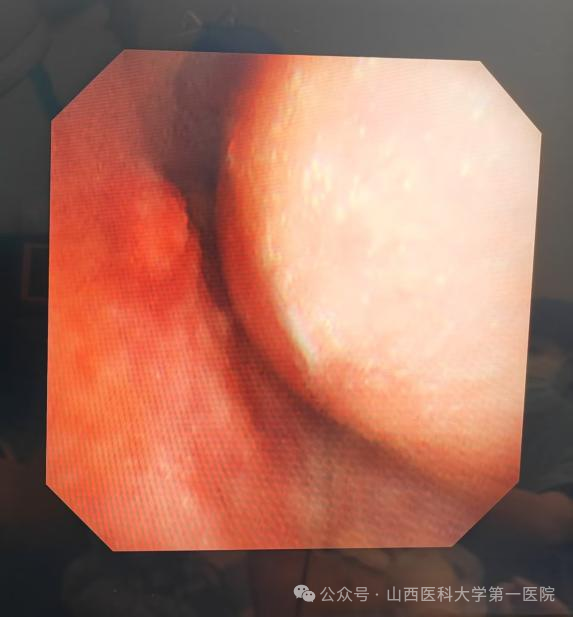

支气管镜下可见气管上端重度狭窄

当日晚上9点,呼吸介入团队成员任寿安、郭志宏、尹建升、李艳青、王琛在手术室为患者在局部麻醉下行支气管镜检查,发现气管上段呈新月形外压性狭窄,管腔狭窄约95%,任寿安、郭志宏主任医师迅速置入气道支架,完全覆盖狭窄部位,麻醉科郭志佳副教授全程保驾护航。整个过程有惊无险,患者呼吸困难得到明显改善,平卧返回重症医学科密切观察。

5月10日下午,重症医学科高海晋医生敏锐察觉到患者血氧饱和度下降,呼吸与危重症医学科呼吸介入团队得知情况后快速响应,尹建升医生与李艳青护士为患者行床旁支气管镜检查,发现气管支架移位,这是气管支架置入术后的常见并发症,经过调整后支架重新支撑起气管狭窄部位。